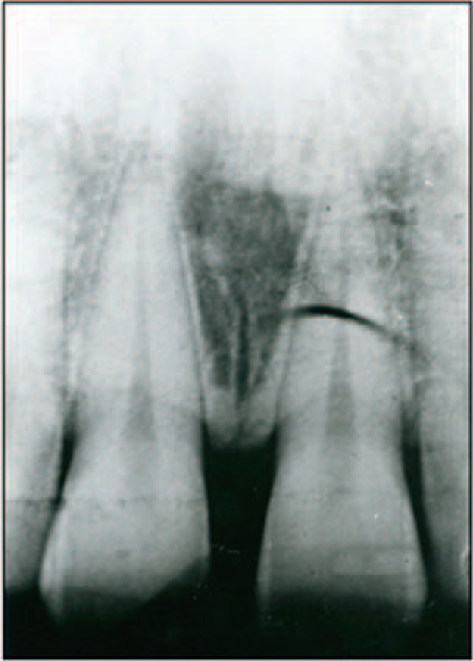

Dilaceration